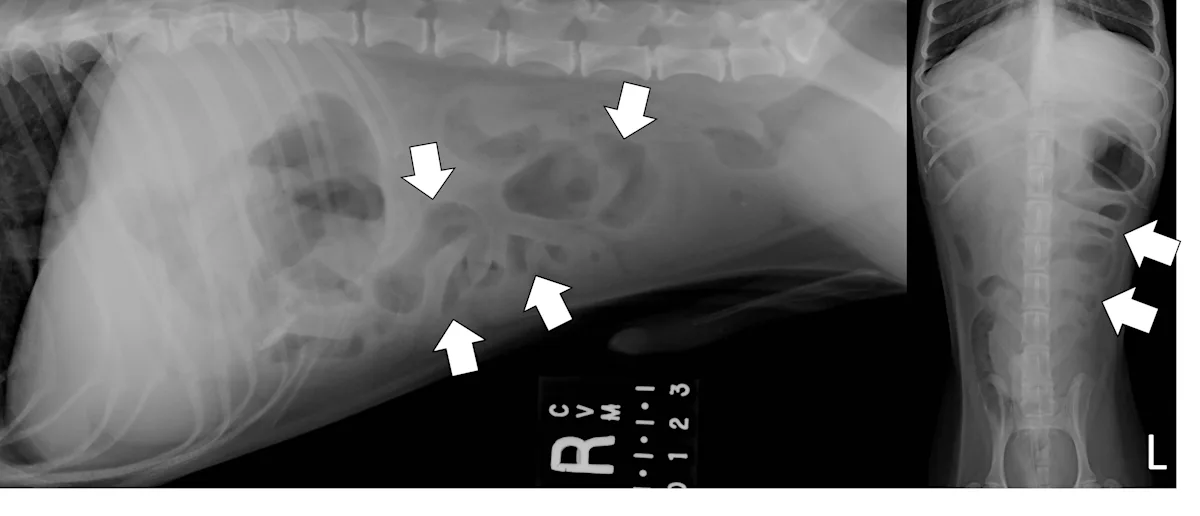

Linear Foreign Body Obstructions

Linear foreign body obstructions occur when an object (eg, string, cloth) becomes stuck orally but extends aborally through the intestinal tract. Peristaltic contractions typically cause the small intestine to travel orally, eventually bunching. As a result, radiographic findings include intestinal bunching (ie, plication; Figures 5 and 6), an undulating serosal border, and angular or crescent-shaped gas bubbles. Obtaining a left lateral projection is critical because many linear foreign bodies anchor in the pylorus.

Right lateral and ventrodorsal abdominal radiographs of a male dog (unknown age, breed, and neuter status) with a surgically confirmed acute linear foreign body (cloth) obstruction. Portions of the small bowel are segmentally dilated with bunching and angular or crescent-shaped gas bubbles (arrows).